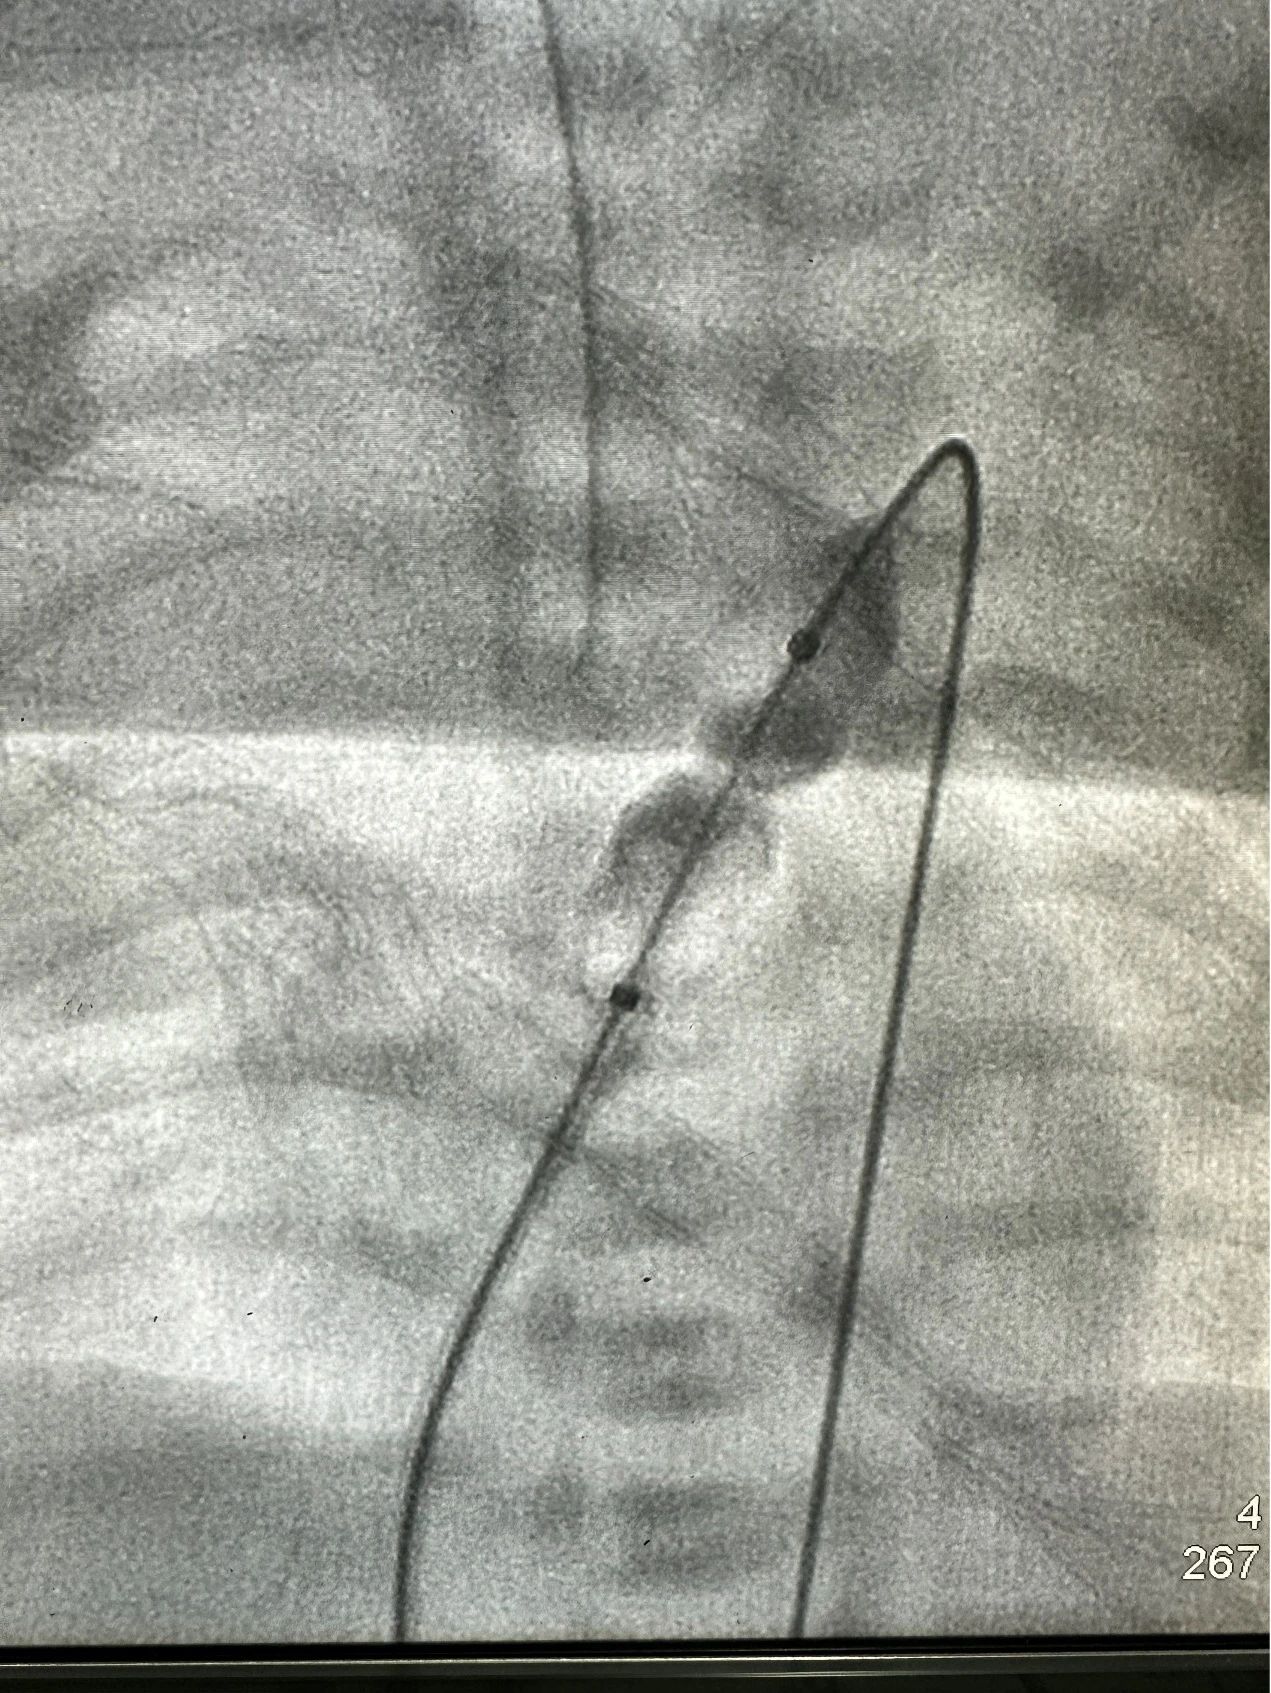

经皮肺动脉瓣球囊扩张手术是一种介入性治疗,通过穿刺血管,将带有球囊的导管沿着血管送到狭窄的肺动脉瓣处后,对球囊进行充盈扩张,从而撑开狭窄的肺动脉瓣,让血液能顺畅地从右心室流向肺动脉。出生仅6天的新生儿血管非常细小,穿刺难度极大,对操作技术要求极高。

1月26日,除夕前两天,谢琦主任医师及窦志副主任医师在麻醉科、手术室的密切配合下,顺利完成了首例新生儿经皮肺动脉瓣狭窄球囊扩张手术。春节期间,孩子在监护病房医护人员的精心治疗下快速恢复正常,各项检查结果满意,于2月9日顺利出院。